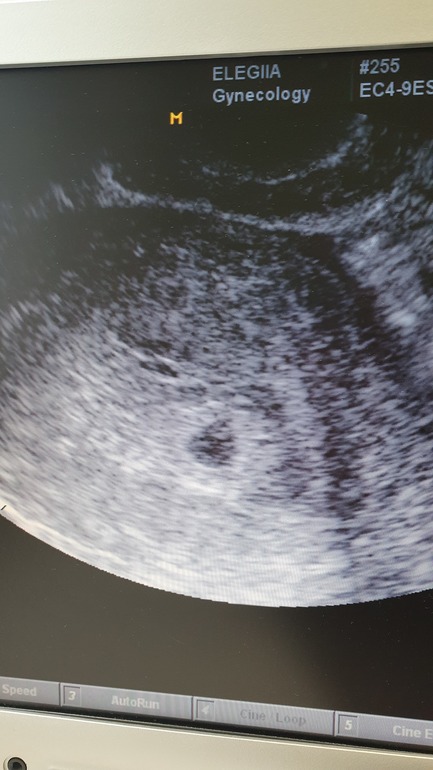

С утра замочила тест, хотя даже и не рассчитывала на беременность, долго не могла понять, что за полоски он выдал, так как сама никогда такие тесты не брала (подруга давно поларила). И вот вообще не ясно, в одном окне плюс, в другом - минус. Побежала сюда спрашивать, пароль от аккаунта не помню, создала пост с какого-то левого гугловского. Все в голос сказали "беременна". Я в шоке, не верю, не понимаю. Может тест брак. Делаю электронный тест, блин, беременна 3+. Да как это может быть с 99% неподвижными сперматозойдами, с 97% морфологически фиговыми сперматазойдами, поликистозом и суперкороткими месячными в 1.5-2 дня. Нас на ЭКО направили в ЦПСиР, дали лист в вагоном анализов и обследований обоим. Мы забадались бегать по врачам и забили на это дело. У меня 2 детей и нам хватит. Не верю. Поехала на УЗИ, а там 3 недели акушерские. Без вариантов, я беременна, это снова чудо, как и с первым ребенком. Но ведь совсем не планировали уже, уже полгода просто забили, смирились и жили себе не тужили. Еще раз подтверждаются слова моего гинеколога "Забеременеть сложно, а залететь - запросто".